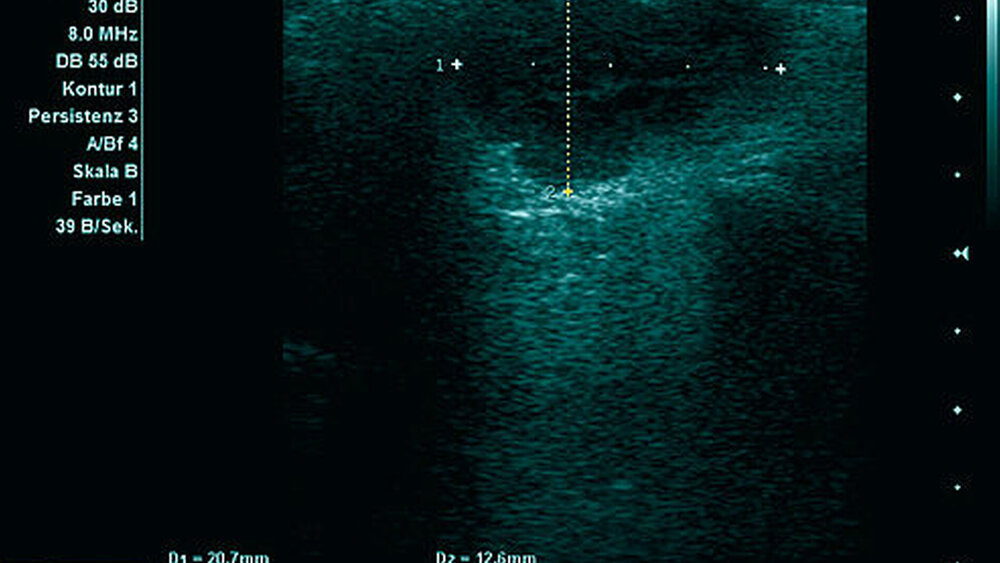

Zur weiteren Diagnostik erfolgte eine Sonografie (Abbildung 2) sowie eine drei- dimensionale Bildgebung mittels MRT (Abbildung 3). Hier zeigte sich eine Formation in der linken Glandula parotis ohne Infiltration der Nachbarstrukturen, die bildmorphologisch am ehesten einem pleomorphen Adenom entsprach.